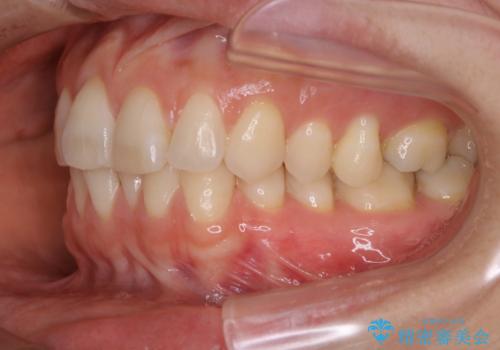

- 下の前歯のがたつきが気になるとの事でご相談にいらした患者様です。

元々はリンガルブラケットをご希望されていましたが、モニター制度を利用してインビザラインによる治療を行いました。

インビザラインFULLで奥歯の噛み合わせから改善させることで、上下の真ん中位置をしっかり合わせることが出来ました。

横顔のシルエットも改善させることができ、大変喜んでいただけました。